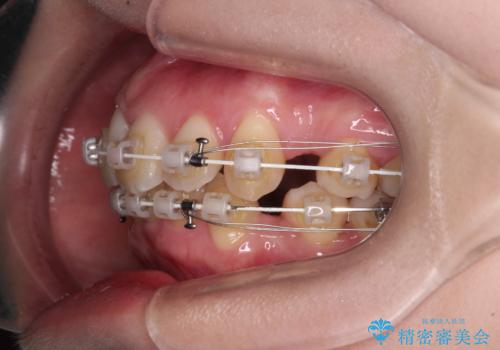

- 審美装置

- 2年9ヶ月

- 10-30回

上下左右第一小臼歯4本を抜歯して、積極的に口元を引っ込めるよう、ワイヤー装置にて矯正治療を行うこととしました。